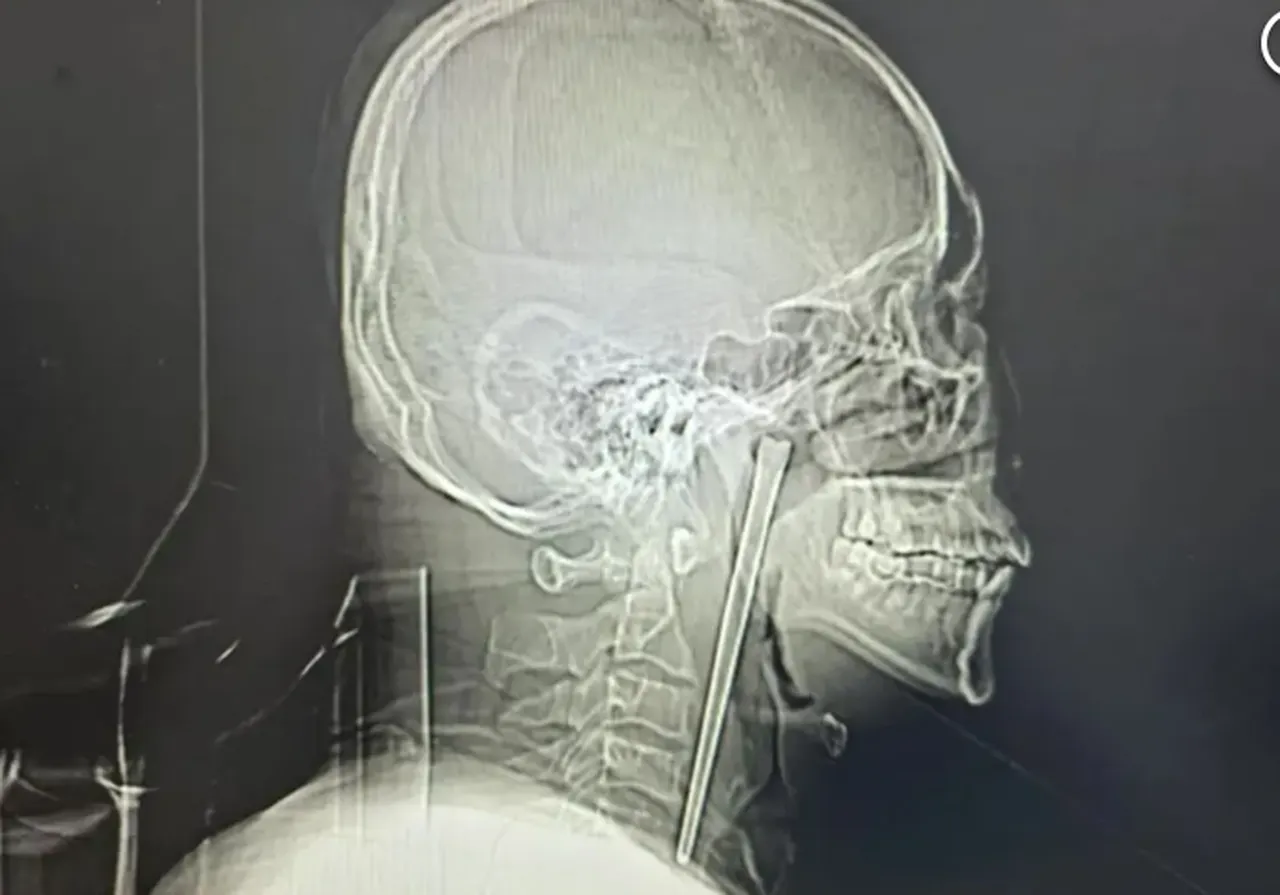

Akıllara durgunluk veren olay, Çin’in Liaoning eyaletinde yaşandı. 2018 yılında bir akşam yemeği sırasında metal bir yemek çubuğu yutan 46 yaşındaki Wang, tam sekiz yıl boyunca boğazında yaklaşık 13 santimetrelik yabancı bir cisimle yaşadı.

South China Morning Post'un haberine göre, alkolik olarak tanımlanan Bay Wang, 2018'de metal çubuğu yuttuktan hemen sonra hastaneye başvurmuştu. Ancak o dönemde doktorların boynuna cerrahi müdahale yapması gerektiğini öğrenince, operasyonu reddederek hastaneden ayrılmıştı.

Cerrahlar, Wang’ın yıllar önce korktuğu geniş çaplı boyun kesisi yerine, ağız yoluyla gerçekleştirilen minimal invaziv bir yöntem kullanarak metal çubuğu çıkarmayı başardılar. Hastane raporunda, metal cismin bunca zamandır orada olmasına rağmen hastanın ses tellerine ve çevredeki mukoza zarına zarar vermediği, hayati fonksiyonlarının normal kaldığı belirtildi. Ameliyatın ardından birkaç gün içinde taburcu edilen Wang’ın sağlık durumunun iyiye gittiği belirtildi.